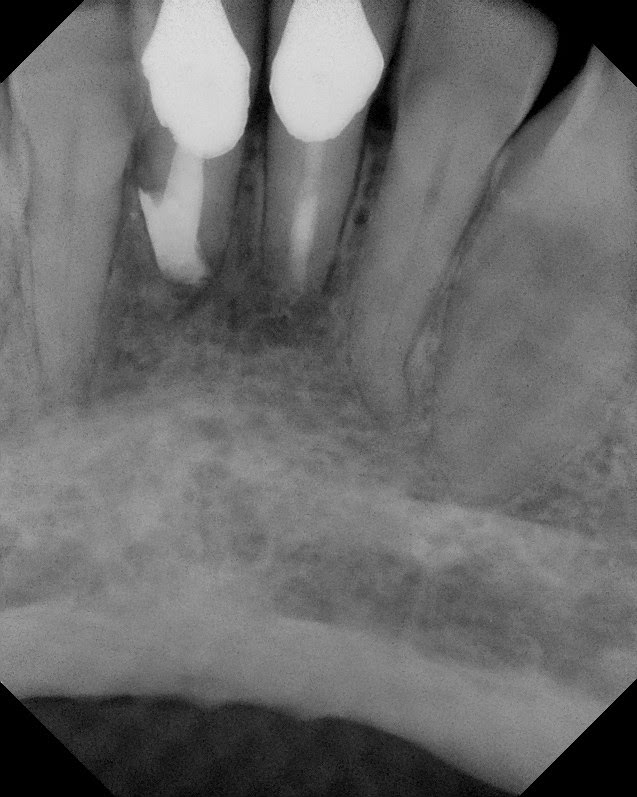

6 month Re-evaluation.